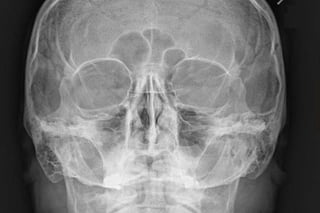

Radiography

Plain X-Ray of the Orbit

• Very limited role

• Indications:

 Traumatic Injuries

 Foreign Bodies

X-Ray Views

• Waters View

• Caldwell’s View

• Lateral View

• Submentovertex View

• Rhese View

Water’s View

a - Frontal sinus

b - Medial Orbital Wall

c - Innominate Line

d - Inferior Orbital Rim

e - Orbital Floor

f - Maxillary Antrum

g - Superior Orbital Fissure

h - Zygomaticofrontal Suture

i - Zygomatic Arch

Orbital Fat

Herniation

Orbital

Emphysema

Orbital Fracture